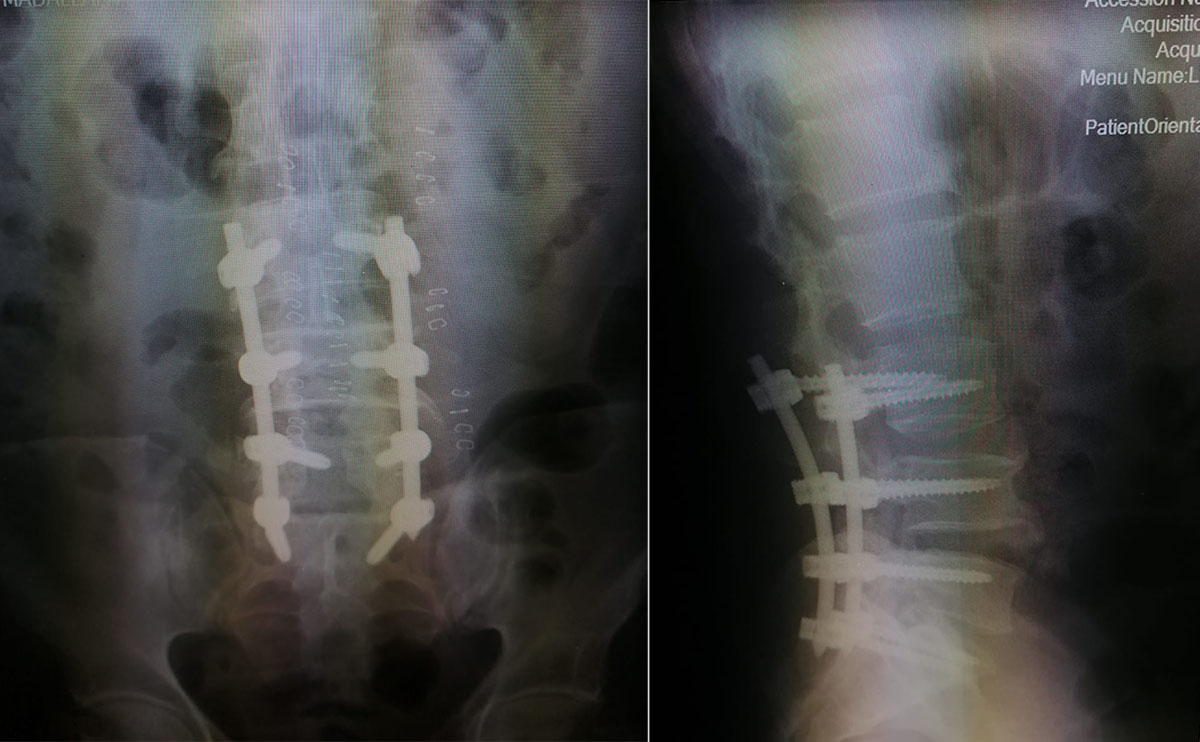

أجريت في مستشفى الكرك الحكومي، عملية تثبيت عبر ثقوب صغيرة بالجلد بالتداخل المحدود، مع إجراء إعادة تحرير لقناة العصب والأعصاب الطرفية من خلال الميكروسكوب ( percautanious 4 level spinal fusion with revision microscopic (lamenectomy لمريض يعاني من ألم شديد أسفل الظهر و خدران في الأطراف مع عدم ثباتية في الفقرات القطنية بالرغم من إجراء عملية سابقة له في مستشفى آخر.

وأجرى العملية فريق طبي من كلية الطب في جامعه مؤتة وأطباء مستشفى الكرك الحكومي، مكون من استشاري جراحة العظام والعمود الفقري الدكتور علاء عقل، واستشاري جراحة الأعصاب الدكتور رائد جردات، واختصاصي التخدير الدكتور اسماعيل أبو الشعر.

وبين مدير المستشفى الدكتور معتز القرالة في بيان اليوم الجمعة، أن المريض بحالة صحية جيدة وعاد إلى منزله بعد 3 أيام من العملية، لافتا إلى أن هذه العملية تجرى لأول مرة في محافظات الجنوب وفي وزارة الصحة.